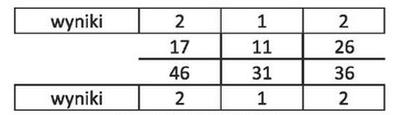

| 1 | 1 | 1 |

| 17-14 | 13-23 | 24-27 |

| 47-44 | 43-33 | 34-37 |

| 1 | 3 | 1 |